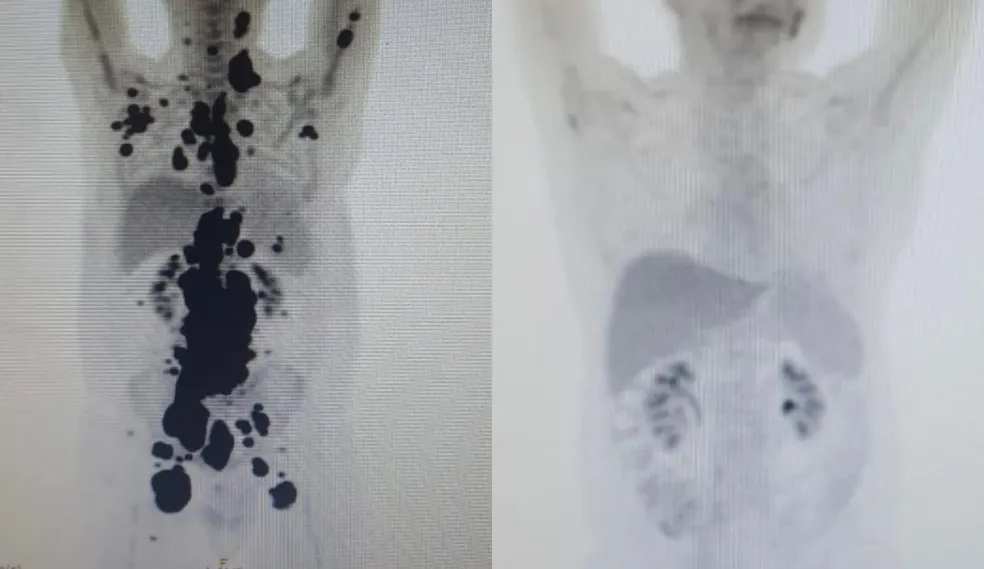

Paulo Peregrino alcança remissão completa após tratamento com CAR-T Cell (Foto: Arquivo Pessoal)

Em abril, Paulo passou pelo tratamento CAR-T Cell, uma terapia que utiliza as células do sistema imunológico do paciente para combater o câncer. Após um mês do tratamento, o paciente atingiu a total remissão de seu linfoma, um grande marco considerando que já estava próximo de dar início aos cuidados paliativos.